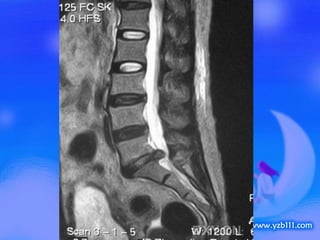

盘突出  磁共振显示腰 5/ 骶 1 椎间